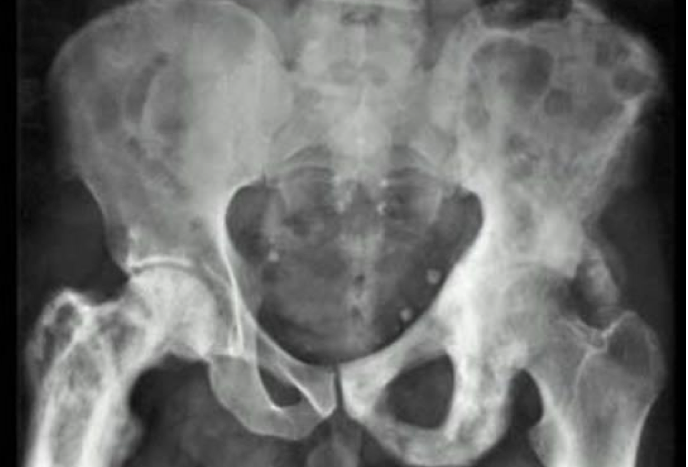

What is this?

Pagets disease